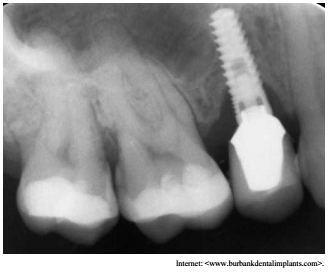

Um paciente que havia recebido implante unitário colocado no lugar do dente 15, não compareceu às visitas de manutenção e retornou dois anos depois, com a condição apresentada na imagem precedente. O tecido mole peri-implantar apresentava sinais clínicos de inflamação, com supuração e sangramento à sondagem.

Com base na situação hipotética e na figura apresentadas, julgue o item que se segue.

A terapia não cirúrgica, mesmo com o uso de antimicrobianos tópicos, demonstrou ser bastante ineficaz no tratamento das peri-implantites, devendo a abordagem cirúrgica ser preferencial na situação apresentada.